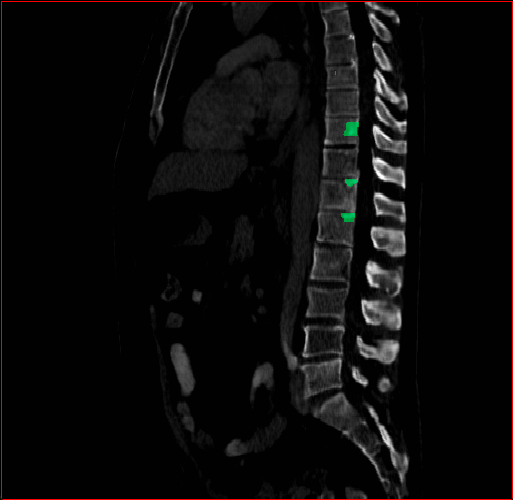

Bone-Les

1×1×1.31\times 1\times 1.3

mm

512×512×384512\times 512\times 384

Figure 5: MAISI-v2 segmentation-guided results for five types of tumors. We show results for different voxel spacing and volume size to demonstrate the flexibility of MAISI-v2. Different Hounsfield Unit window is used to better show the contrast between tumor and normal tissues.